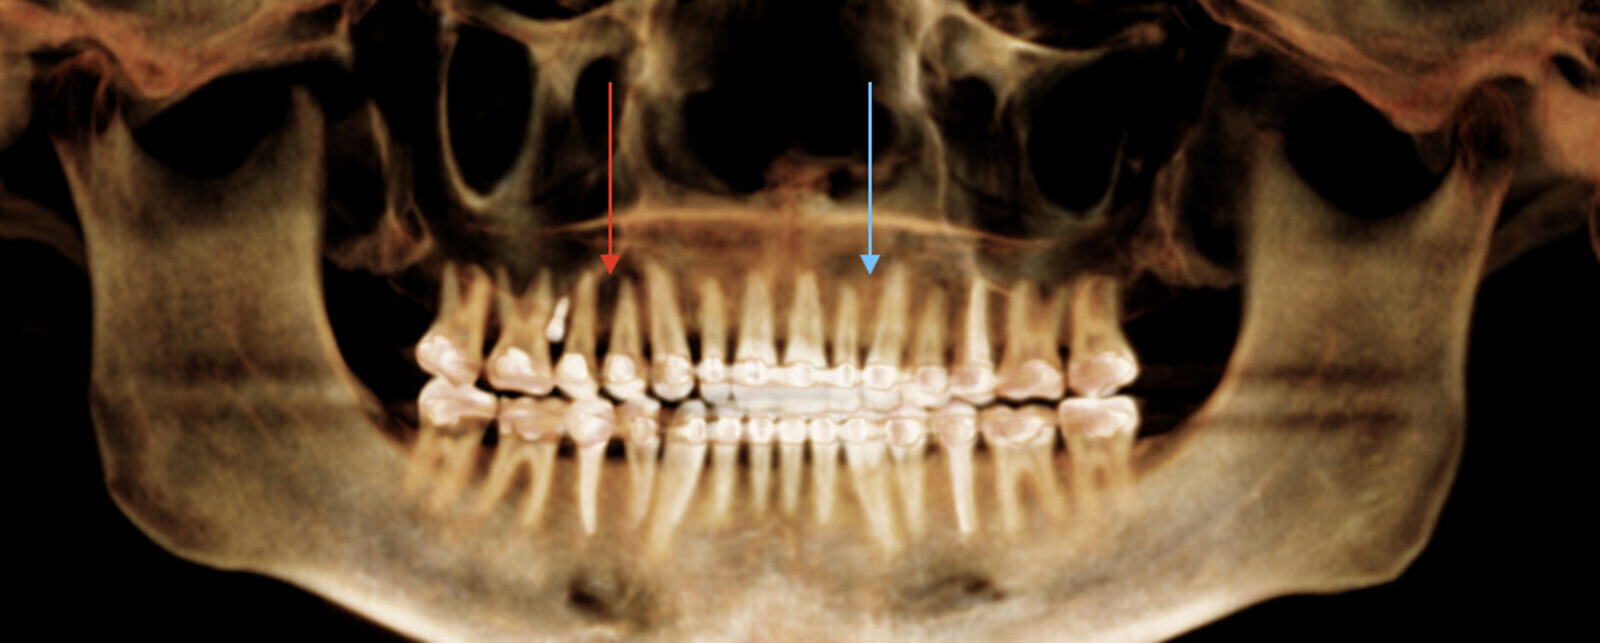

Clearly, TAD placement will be determined in part by the mechanics they are used for. In addition to the mechanics used for TAD anchorage, there are important factors of individual anatomy that should be considered. A recent cone beam computed tomography scan, or panoramic radiograph, should first be obtained. This radiograph can be used to evaluate root divergence, bone height and, to some extent, bone density. Figure 1 demonstrates two areas indicated by both red and blue arrows. The red arrow indicates a radiolucent area, indicative of lower bone density. This would be an area where TAD placement would not be indicated. In contrast, the blue arrow indicates a radiopaque area, suggesting greater bone density and an area thus more ideal for TAD placement.